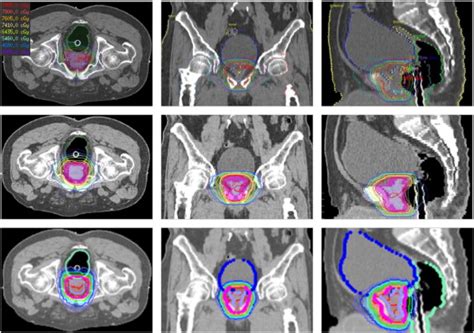

690×440

semanticscholar.org

Figure 1 from Analysis of Radiation Treatment Planning Results for ...